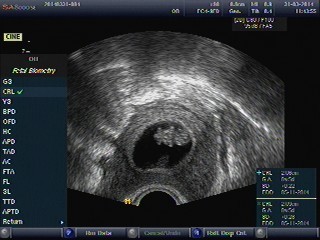

Holky jsem zpět z dnešní kontroly. Vše je v pořádku. Prcek byl dnes na UZ krásný, takový malý sněhuláček a dala se rozeznat hlavička a výrustky na nožky a ručky. Srdíčko tluče a odpovídáme těm 8+5tt přesně jako dle MS. Dostala jsem už těhotenskou průkazku a na 29.4. jsem objednaná na NT screening. Čekám, že mi mailem zase dorazí fotečka, tak pak se pochlubím. Jsem moc šťastná 🙂 Od zítřka mám vypsanou neschopenku, vycházky 13-19h a dr řekla, že kdyby mě nenašla kontrola dopo doma, ať za ní přijdu, že mi potvrdí kontrolu. Je fakt skvělá. Další KO zase za týden (7.4.), já prostě zatím déle s nervy nevydržím, snad to postupně poleví. Dneska jsem zase byla napnutá jak struna.